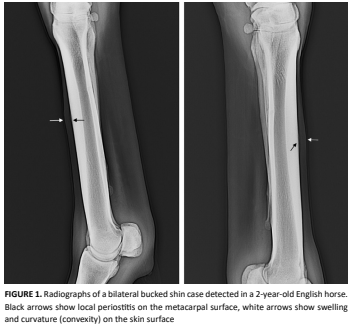

Medicina Veterinaria